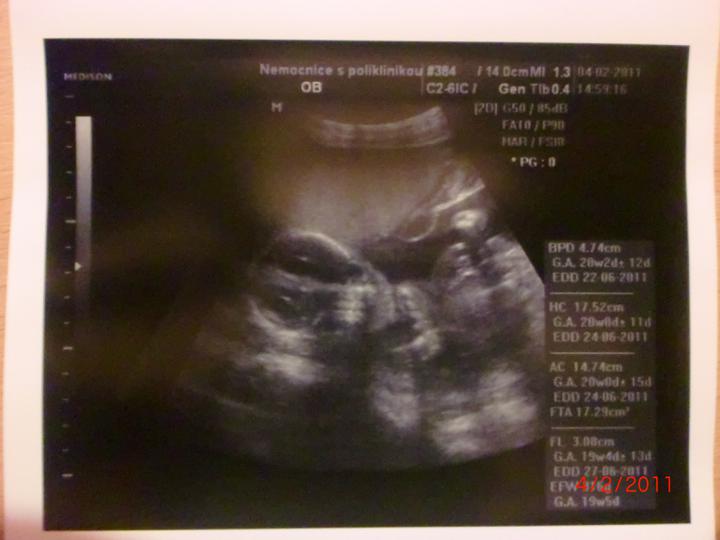

Doktor mi začátkem listopadu 2007 vysadil HA z důvodu zdravotních potíží,dávali jsme si tedy pozor a čekali,zda potíže ustoupí,ale 31.prosince 2007 mi manža řekl,že by chtěl miminko,byla jsem z jeho návrhu vykulená,ale byla to překrásná představa a tak jsem souhlasila..Od 8.ledna 2008 jsme se tedy začali snažit o miminko,začala jsem pít kontryhel a zobat Calibrum babyplan,aby mému tělu nic nechybělo 🙂 Nechávali jsme tomu volný průběh,ani jeden z nás na to nijak nepospíchal,nevím,proč jsem si říkala : Do roka se to snad povede 😀 A 29.3.2008 jsem měla pozitivní testík,sama jsem nechápala,jak brzy se to povedlo 🙂 Byla jsem neskutečně šťastná a stále jsem 🙂 Termín porodu dle MS 5.12.2008 a dle utz ve 12.tt 30.11.2008 Už od začátku jsem tušila,že čekám kluka a tak hned z první kontroly v 5.tt jsem si koupila modré bačkůrky pro štěstí,které se mnou chodili na každou kontrolu 🙂 Od 15.tt mi začalo celkem hodně tvrdnout břicho a chvilkama to bylo velice nepříjemné,na další kontrole,to jsem byla 18+4 , jsem to doktorovi řekla,ten mi pověděl,že se mu to vůbec nelíbí a tak mě poslal na utz,na utz jsem čekala 2 hodiny a můžu říct,že to byli nejhorší 2 hodiny v mém životě,tolik jsem se o miminko bála,ten strach,že něco není v pořádku byl opravdu k nevydržení..Přišla na mě řada a tak jsem tedy šla do kabinky a následně na lehátko na utz,pan doktor konstatoval,že všechno vypadá v pořádku a že se nemám bát,předepsal mi magnezium a že by to mělo pomoct,navíc koukám na ten utz a povídám panu doktorovi,to co tam vidím jsou kouličky? 😀 A on že jistě,že si myslel,že už to dávno vim,když se tak krásně ukazuje 😀 ,můj doktor mi řekl,že zřejmě porodím předčasně,což mě celkem vyvedlo z míry..Ale jsem optimisticky naladěnej človíček a tak jsem Honzíkovi vysvětlovala,že v bříšku musí ještě zůstat..Ve 20.tt jsem šla na velkej UTZ,kde mi opravdu řekli,že Honzík je zdravej a opět Honzík ukázal,že je 100% chlapeček 😀 Ve 26.tt jsme jeli na 4D utz do Liberce,tam se Honzík ukázal zas,no za celé těhu se nestalo,že by se na utz neukázal aa neroztáhl nožičky,máme malýho exibouše 😀 Ve 30.tt mě čekal další UTZ,vše v pořádku,Honzík už byl hlavičkou dolů a vážil 1600g ..Ve 35.tt mě doktor opět kvůli tvrdnutí břicha poslal už do ambulance,aby se o mě starali už tam.. Ten den jsem strávila v nemocnici 7hodin,fakt děsný !!! 2 hodiny čekání u mého doktora,ten mě tedy poslal už do nemocnice,takže jsem musela na UTZ,tam jsem čekala 2 hodiny,pak na natáčky,tam jsem čekala hodinu a pak na ambulanci a tak jsem čekala zas dvě hodiny ☹ Na UTZ ve 36.tt měl Honzík už 2600g ..